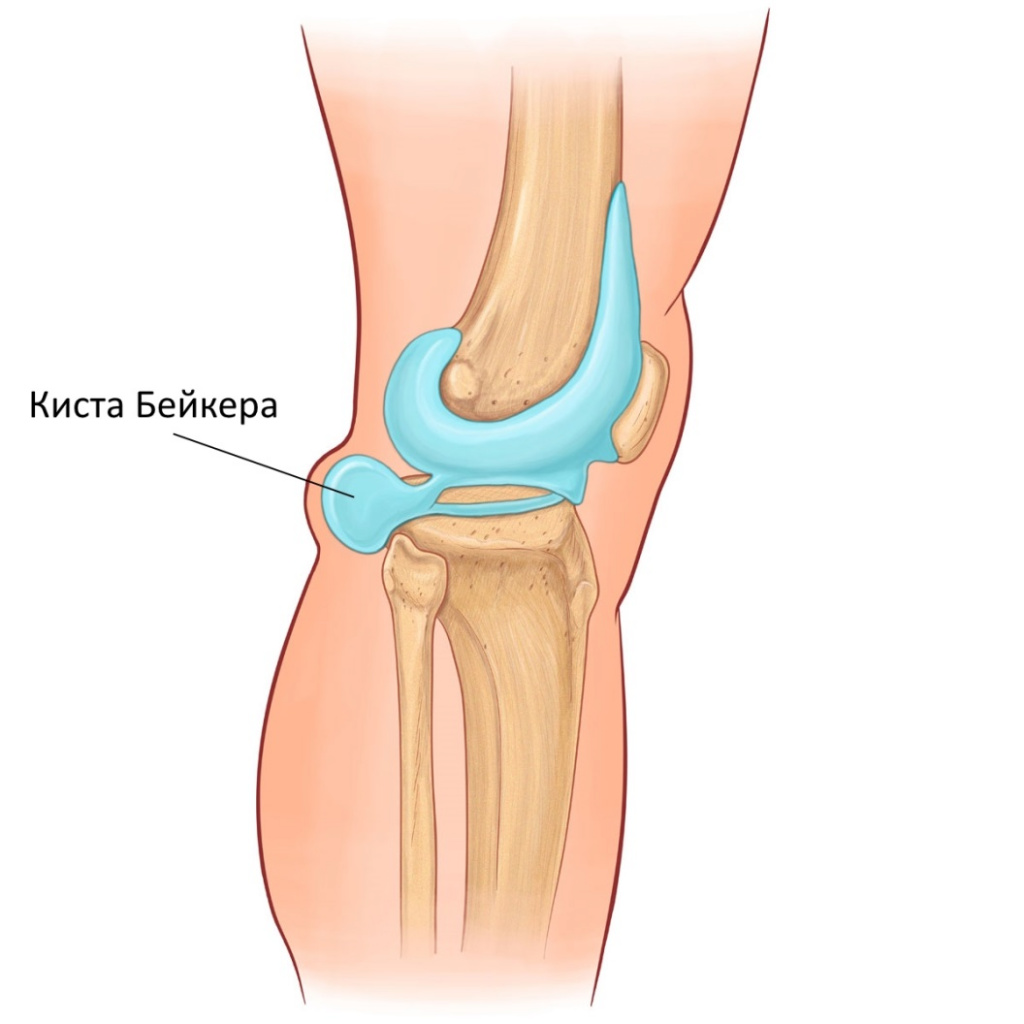

Фото и диагностика кисты Бейкера